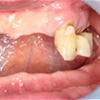

2.固定物埋入的手术

经过手术将类似牙根形态的植入体植入(上下)颚的骨组织内,(fixture)。手术会进行局部麻醉,可以放心接受手术。